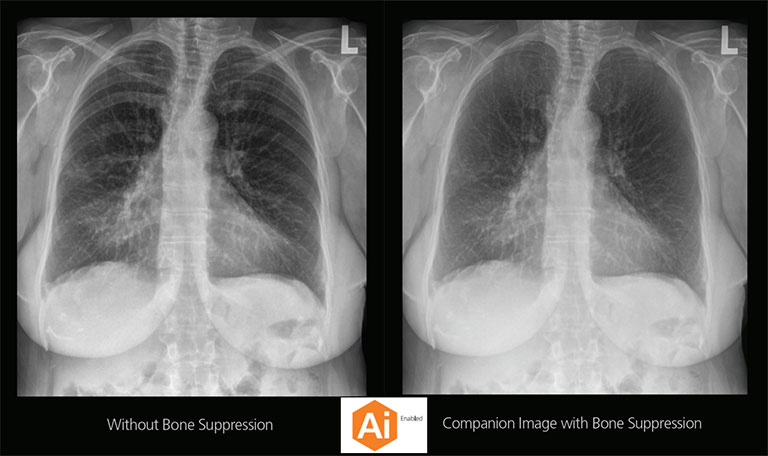

Carestream Introduces New Software Update to Boost Diagnostic Accuracy

Carestream today announced the latest update to its Image Suite V4 Software, MR 11: a series of enhancements to help improve customer confidence and increase diagnostic accuracy [...]

CARESTREAM Image Suite V4 MR11 has set a new standard for workflow efficiency, offering a robust set of features and functionalities to enhance clinical confidence in healthcare professionals. Using an auto-generated companion image from a single exposure, leverage a range of image processing options to increase diagnostic accuracy and enhance patient care.